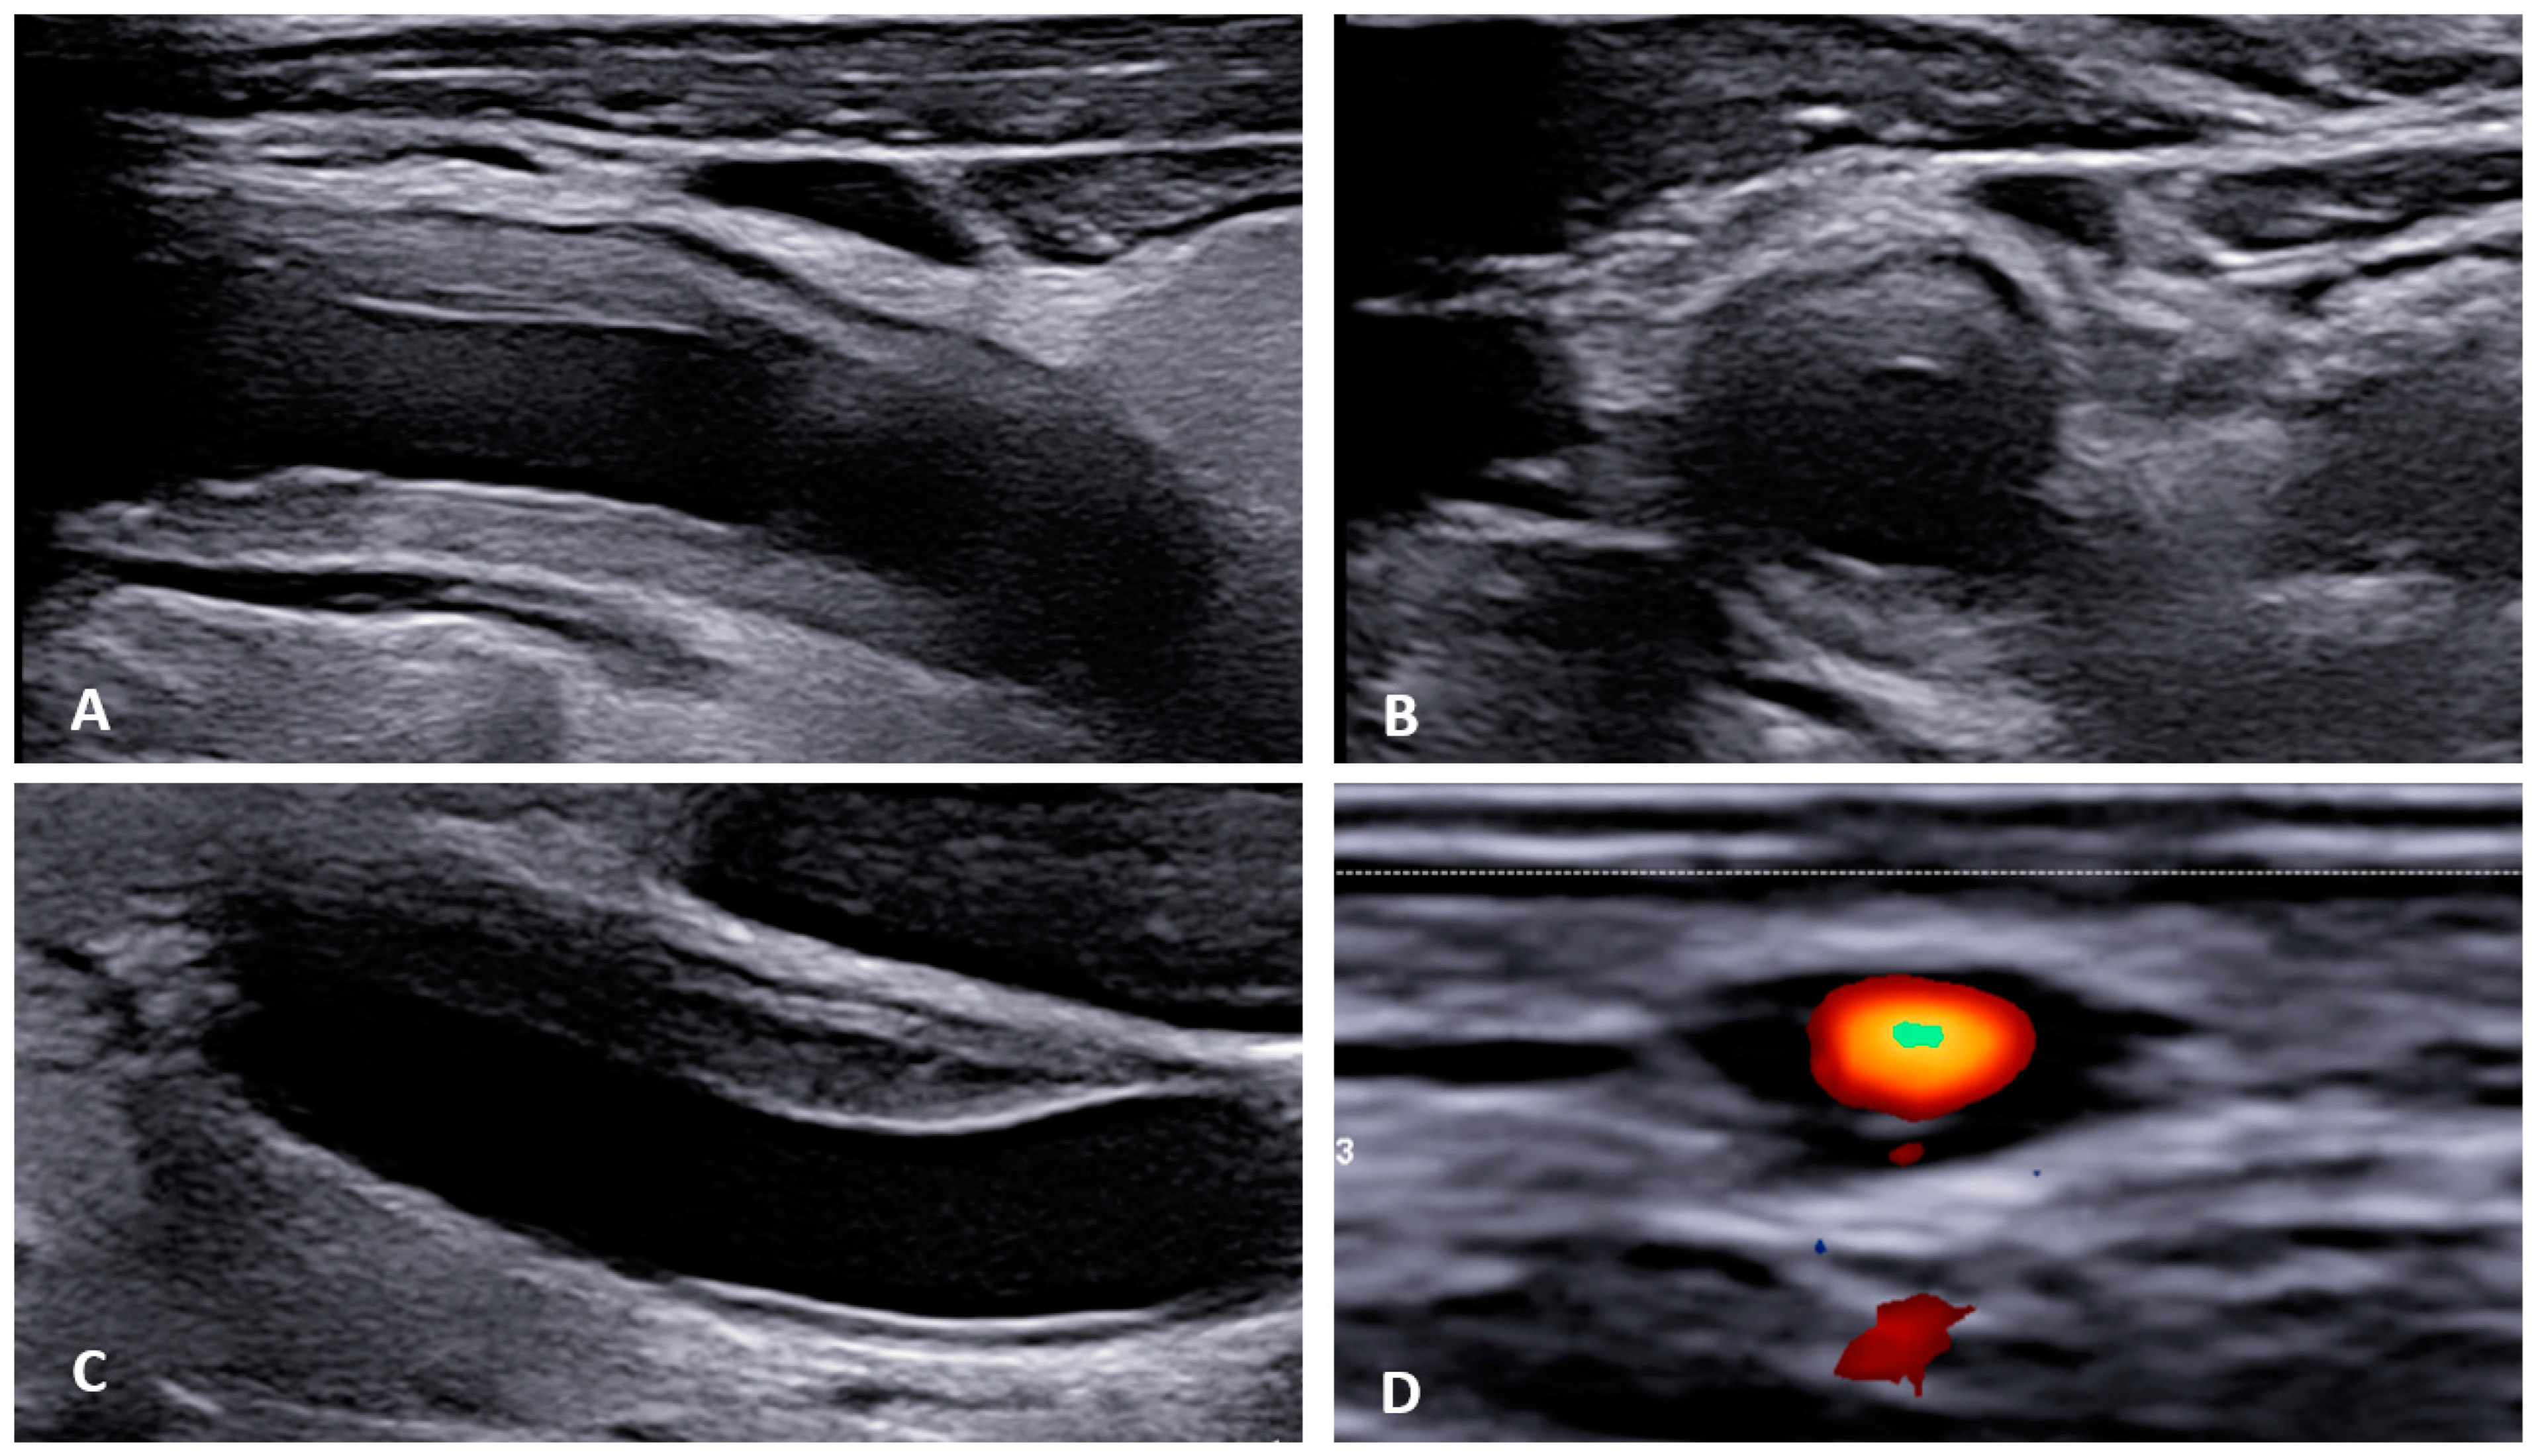

Figure 2. Ultrasonographic findings in patients with large vessel vasculitis: (A,B): B-mode US with the finding of concentric carotid intima-media thickening in a patient with Takayasu’s arteritis ((A) longitudinal plane, (B) transversal plane). (C). B-mode US: carotid intima-media thickening in a patient with giant cell arteritis. (D): Power Doppler US in a patient with temporal arteritis (typical “HALO” sign). Courtesy of Dr. Konstantinos Triantafyllias, Rheumatology Center, Rhineland-Palatinate.

Figure 4. Pronounced wall thickening of the temporal arteries, as depicted on black blood magnet resonance imaging sequences (T1 space). (Courtesy of Dr. Corinna Schorn, Rheumatology Center, Rhineland-Palatinate).